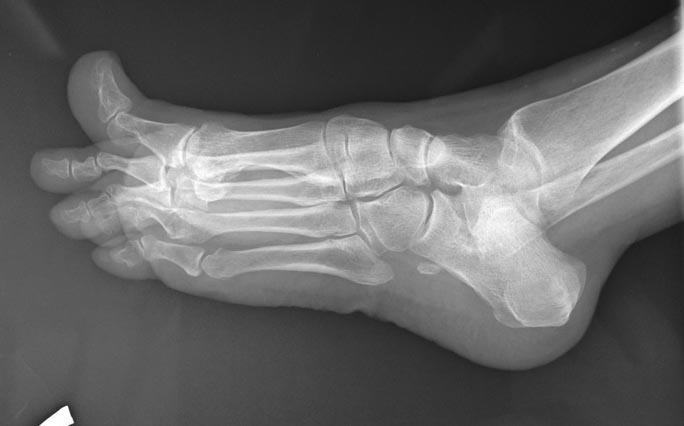

Пциентка Н, 58 лет. Больна с 2005г. Лечилась консервативно. Со слов, тогда было сильное искривление 1,2,3,4 пальцев в латеральную сторону.

В 2012г. операция: коррекция деформаций 1,2,3, 4 пальцев.Рецидив. В 2013г. – коррекция деформации 2,3,4 пальцев. С ноября 2014г. рецидив деформации 1,2,3,4 пальцев. Возможные варианты коррекции?

А что беспокоит пациентку? Есть ли натоптыши на подошве? Болит ли первый плюснефаланговый сустав? Или еще где болит? Лечим ведь пациента, а не деформацию. Если же исходить из имеющихся данных и отсутствия информации о ранее выполненных операциях, то необходимо выполнить обратную остеотомию Akin, чтобы устранить hallux varus; укорачивающие остеотомии 1-4 плюсневых костей (первой - для декомпрессии первого плюснефалангового сустава, поскольку имеются признаки его тугоподвижности - установка основной фаланги в положении подошвенного сгибания, а также hallux hyperextensus. Второй-четвертой плюсневых для того, чтобы легче было устранить отклонение кнаружи соответствующих пальцев). Остеотомии (дистальные) 2-4 плюсневых лучше не фиксировать. И выполнить остеотомии оснований основных фаланг 2-4 пальцев, которые зафиксировать на 4-5 недель повязкой в нужном положении, не прибегая к остеосинтезу. Конечно, оптимальным в подобном случае является чрескожный метод (выполнение остеотомий через проколы кожи).